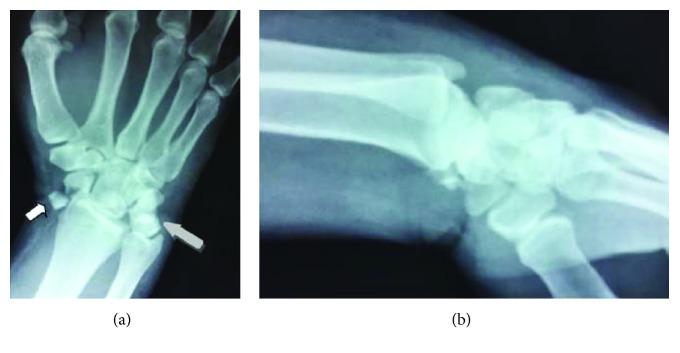

Perilunate dislocation and fracture dislocations are rare injuries corresponding to 10% of all carpal injuries. They usually come with high-energy trauma, with associated injuries representing 61%. Volar lunate dislocation or fracture-dislocation accounts for 3% of perilunate injuries. We present a case of a 42-year-old polytrauma male, transmitted to our department 48 hours after a car accident with a trans-scaphoid volar lunate dislocation. During operation, the lunate was displaced volarly to the ulnar side of the wrist, forward to the styloid process of the distal ulna, while the scaphoid fracture appeared at the waist with comminution, and the proximal pole of the scaphoid protruded under the dorsal capsule. Carpal injuries are often missed out in polytrauma patients, and these injuries are underestimated because of the severity of the other visceral or extremity lesions. Untreated or improperly treated, those injuries lead to serious morbidity and loss of function. Therefore, good functional prognosis with decreased percentage of complications can be achieved following early recognition and early open surgical ligamentous complex repair.

月骨周围脱位和骨折脱位是罕见的损伤,占所有腕骨损伤的10%。它们通常伴有高能创伤,相关损伤占61%。掌侧月骨脱位或骨折脱位占月骨周围损伤的3%。我们报告一例42岁的多发伤男性患者,在车祸后48小时被送至我院,诊断为经舟骨掌侧月骨脱位。手术中,月骨向掌侧移位至腕部尺侧,向前移位至尺骨远端茎突,同时舟骨腰部出现粉碎性骨折,舟骨近端在背侧关节囊下突出。多发伤患者常漏诊腕骨损伤,且由于其他内脏或肢体损伤的严重性,这些损伤被低估。未经治疗或治疗不当,这些损伤会导致严重的发病率和功能丧失。因此,早期识别并早期进行开放性手术修复韧带复合体,可获得良好的功能预后并降低并发症发生率。